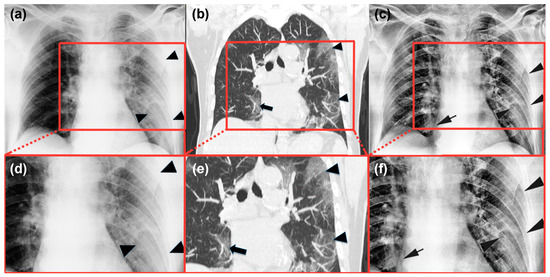

4.2. Radiological Evaluation and Statistics